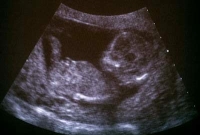

A kutatók 30-38 hetes magzatokat vizsgáltak: az anya hasán keresztül félpercenként „vibroakusztikus” ingernek – hangnak és rezgésnek – tették ki őket, reakcióikat pedig ultrahang segítségével követték nyomon. Ha a magzat egy idő után már nem reagált az ingerre, az azt jelentette, hogy hozzászokott, vagyis „biztonságosnak” ítélte.